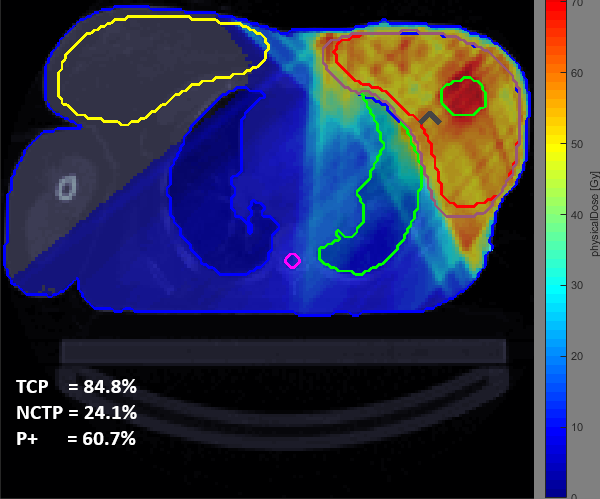

ROBERTA, Robust Biologically Optimized Radiation Therapy

Biologically Optimized Radiation Therapy uses radiobiological models, describing tissue response to ionizing radiation, to improve the quality of Radiation Therapy. We are developing models and algorithms for biologically optimized inverse treatment planning considering explicitly the uncertainties present during the treatment. With increasingly detailed dose-response models, the effectiveness of new treatment strategies can be tested before these are proposed for clinical trials.

What do we do? radiobiological modelling, software development, treatment planning comparison, assessment of the impact of uncertainties

Collaborations with: INESC Coimbra (Portugal), German Cancer Research Center – DKFZ (Germany)

Interested in knowing more about this topic? Contact people: Brígida Ferreira, Ana Margarida Mota

Accepting internships, Masters and PhD!